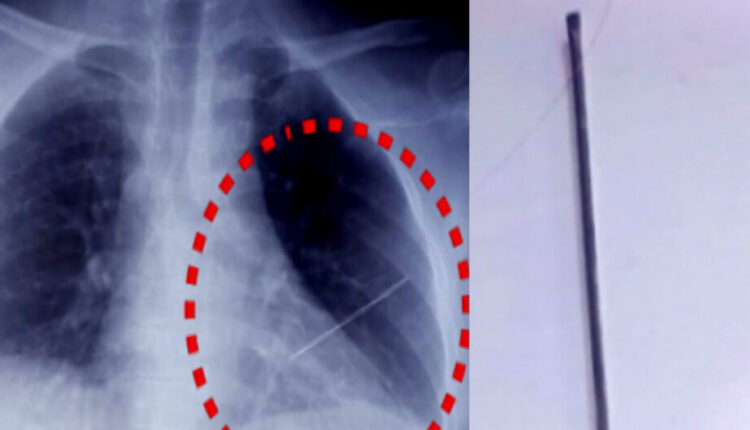

ଭୁବନେଶ୍ୱରର ନିବାସ ଶର୍ମା ନାମକ ୫୧ ବର୍ଷୀୟ ଜଣେ ବ୍ୟକ୍ତିଙ୍କ ଛାତିରେ ଅସାବଧାନତା ବସତଃ ଏକ ଛୁଞ୍ଚି ପଶି ରହିଯାଇଥିଲା। ବିଭିନ୍ନ ମେଡିକାଲରୁ ନିରାଶ ହେବାପରେ ସେ ଏସସିବିରେ ଆଡମିଟ ହୋଇଥିଲେ।

ମେଡିକାଲର କାର୍ଡିଓଥୋରାସିସ ବିଭାଗ ମୁଖ୍ୟ ଡାକ୍ତର ମନୋଜ ପଟ୍ଟନାୟକଙ୍କ ନେତୃତ୍ୱରେ ଏକ ତିନି ଜଣିଆ ଡାକ୍ତରୀ ଟିମ୍ ଏହି ବିରଳ ଅପରେସନ କରି ରୋଗୀଙ୍କ ହୃଦପିଣ୍ଡରୁ ସୁରକ୍ଷିତ ଭାବେ ଛୁଞ୍ଚି ବାହାର କରିଛନ୍ତି। ଏବେ ରୋଗୀ ଜଣକ ସୁସ୍ଥ ଅଛନ୍ତି।

ଏନେଇ କାର୍ଡିଓଥୋରାସିସ ବିଭାଗ ମୁଖ୍ୟ ଡାକ୍ତର ମନୋଜ ପଟ୍ଟନାୟକ କହିଛନ୍ତି, ଏହି ଚ୍ୟାଲେଞ୍ଚ ଆମ ପାଇଁ ଏକ ସୁଯୋଗ । ଭୁବନେଶ୍ୱରର ଜଣେ ୫୧ ବର୍ଷୀୟ ବ୍ୟକ୍ତିଙ୍କ ଛାତିରେ ଛୁଞ୍ଚି ପଶି ହୃତପିଣ୍ଡରେ ଲାଗି ଯାଇଥିଲା। ବିଭିନ୍ନ ହସ୍ପିଟାଲରେ ଦେଖାଇ ସେ ନିରାଶ ହୋଇଥିଲେ। ଏଥିନିମନ୍ତେ ଲକ୍ଷାଧିକ ଟଙ୍କା ଦରକାର ବୋଲି ଅନ୍ୟ ମେଡିକାଲ ପକ୍ଷରୁ ତାଙ୍କୁ କହିଥିଲେ। ଏହାପରେ ସେ ଏସିବି ଆସିଥିଲେ।

ଗତ ୧୦ରେ ରୋଗୀଜଣକ ଏସସିବିରେ ଆଡମିଟ୍ ହୋଇଥିବା ବେଳେ ଗତକାଲି ଅପରେସନ ହୋଇଥିଲା। ଆଜି ଅବସ୍ଥା ଠିକ୍ ଅଛି। ଏହା ବହୁତ ଚ୍ୟାଲେଞ୍ଜପୂର୍ଣ୍ଣ ଥିଲା। କାରଣ ହୃତପିଣ୍ଡ କାମ କରିବା ବନ୍ଦ କଲେ ମଣିଷ ବଞ୍ଚିବା ସମ୍ଭାବନା ନୁହେଁ। ଦୀର୍ଘ ୩ରୁ ସାଢେ ୩ ଘଣ୍ଟା କାଳ ଧରି ଏହି ଅପରେସନ ଚାଲୁ ରହିଲା। ବିଭିନ୍ନ ବିଭାଗୀୟ ମୁଖ୍ୟଙ୍କୁ ନେଇ ଗଠିତ କମିଟି ଏହି ଅପରେସନ କରିଛନ୍ତି।

ପ୍ରଥମେ ରୋଗୀ ଏବେ ଆଇସିୟୁରେ ଅଛନ୍ତି । ୫ ଦିନ ସେଠାରେ ରହିବେ। ତା’ ମଧ୍ୟରେ ଇନଫେକ୍ସନ ନ ହେଲେ ସାଧାରଣ ୱାର୍ଡକୁ ଆସିବେ ବ୍ଲି କହିଛନ୍ତି ଡାକ୍ତର ମନୋଜ ପଟ୍ଟନାୟକ।